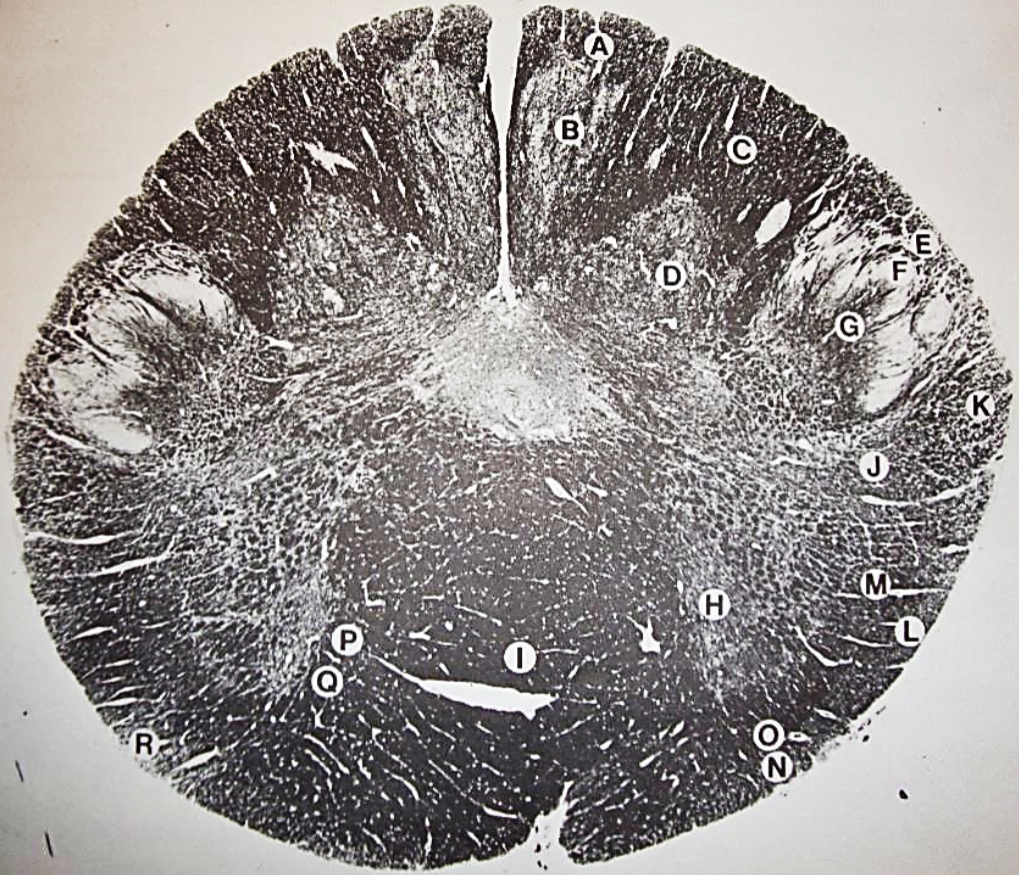

A

Fasciculus gracilis

B

gracile nucleus

C

fasciculus cuneatus

D

cuneate nucleus

E

spinal trigeminal tract

F+G collectively

spinal trigeminal nucleus

H

accessory nucleus

I

pyramidal decussation

J

rubrospinal tract

K

posterior spinocerebellar tract

L

anterior spinocerebellar tract

M

lateral spinothalamic tract

N

anterior spinothalamic tract

O

lateral vestibulospinal tract

P

medial longitudinal fasciculus

Q

tectospinal tract